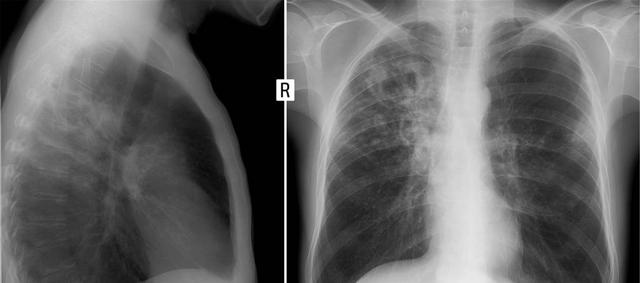

这个应该是2019年开始的,当时王大爷被诊断出肺部有个结节,大概1厘米大小,医生建议他保守治疗。随即,医生得知王大爷的生活习惯很差,每天要抽一包烟,于是医生警告他,如果继续吸烟,这个结节可能会变成肺癌。

当这些固体颗粒进入肺部时,可以完全堵塞肺泡,从而影响肺部的扩张。像上面的王叔叔,有肺结节。如果继续喝茶抽烟,结节会越来越大,肺癌的进程也会加快。